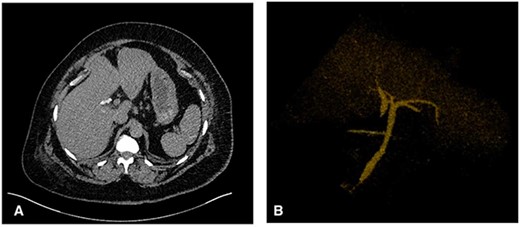

Intraoperatively, standard 4 port laparoscopy was performed, and an oedematous gallbladder was encountered which required a combination of sharp and blunt dissection. The hepatocystic triangle dissection was challenging due to severe fibrosis. A ductal structure was isolated and seen to be entering the gallbladder which was subsequently clipped and a ductotomy performed. After cannulation of the ductotomy, an intraoperative cholangiogram (IOC) revealed what appeared to be a duplicated CHD separating the right and left hepatic drainage systems with a communicating aberrant extrahepatic duct (Fig. 2). Of note, no filling defects were appreciated in the distal common system.

(A) IOC showing the point of cystic duct cannulation with retrograde contrast injection revealing a connection with a duplicated CHD draining the right system and another CHD draining the left system proximally. (B) and (C) Further contrast injection demonstrating no filling defects in the distal common system with good flow into the duodenum.